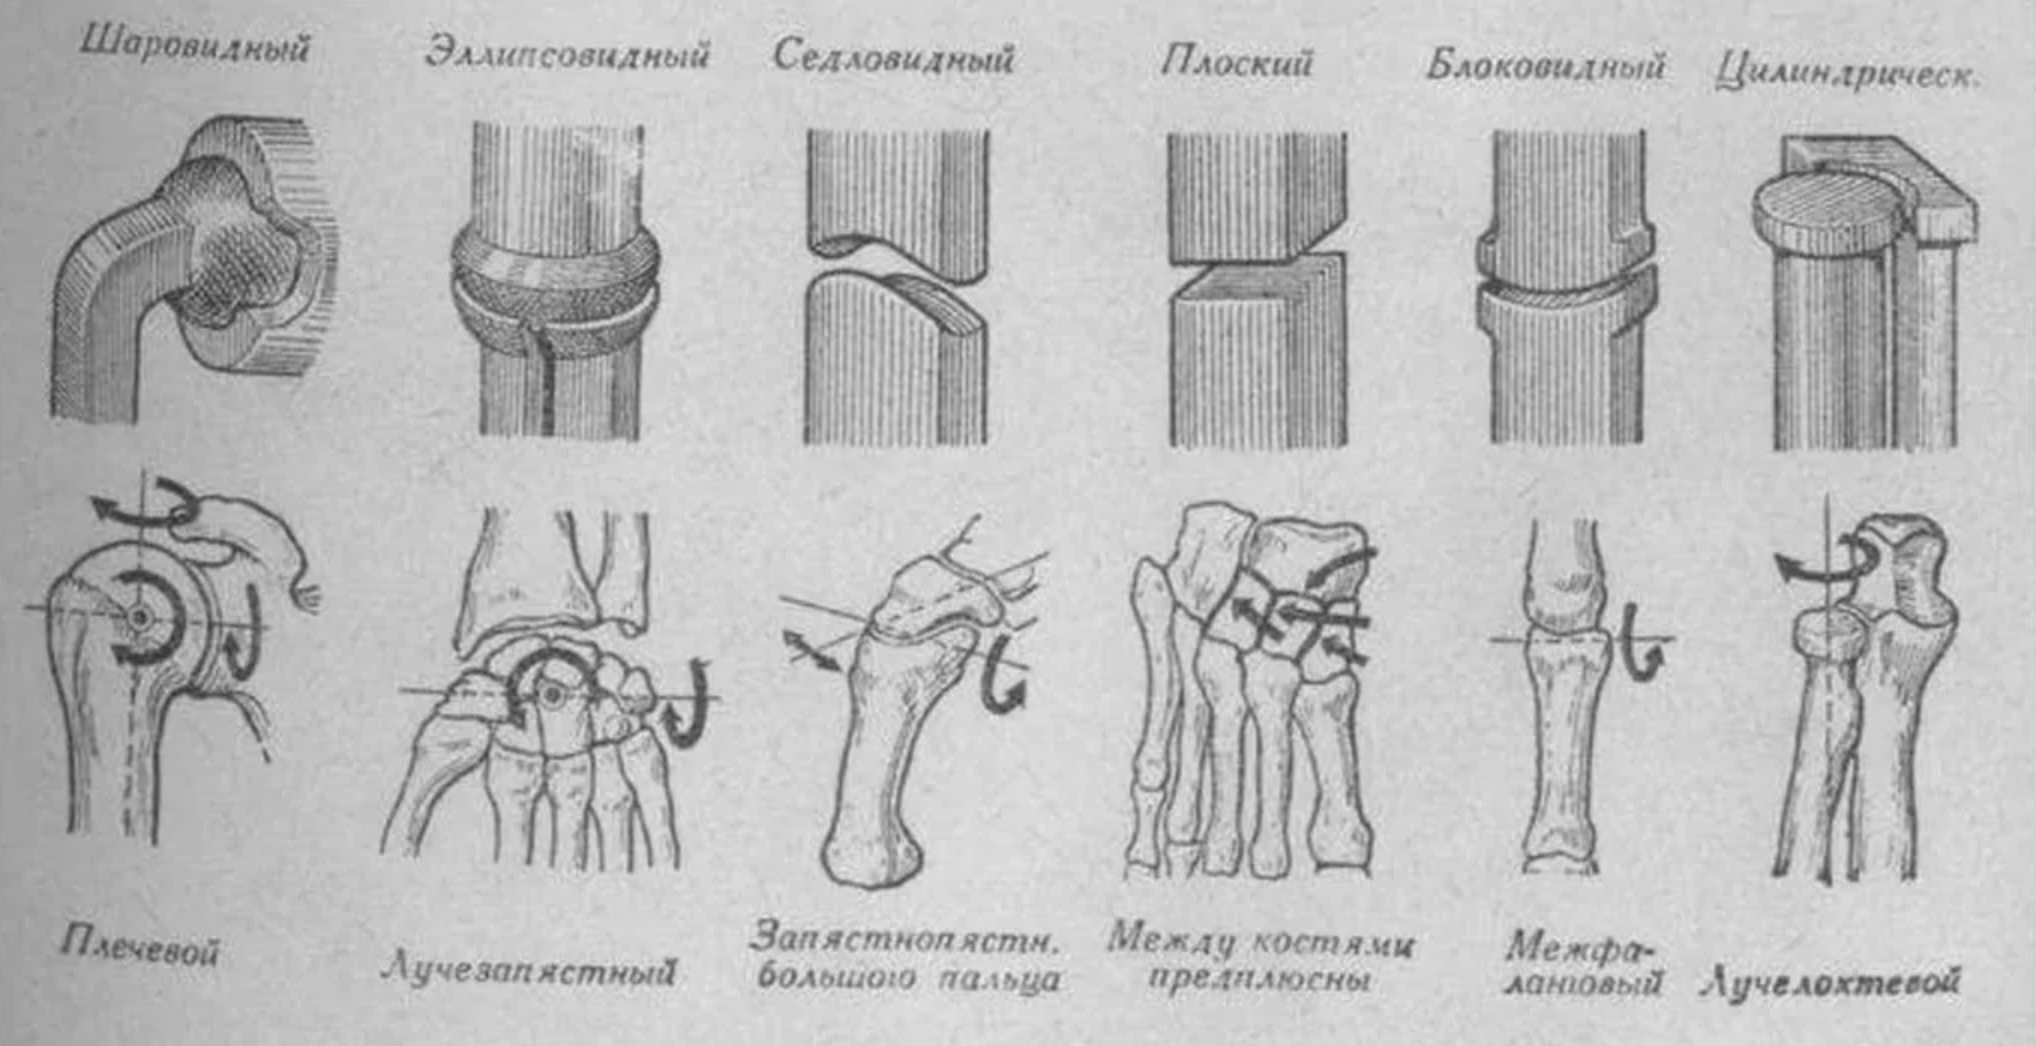

Анатомия суставов Шапарова и Лисфранка: фото и информация

Раздел: Мудрость в деталях